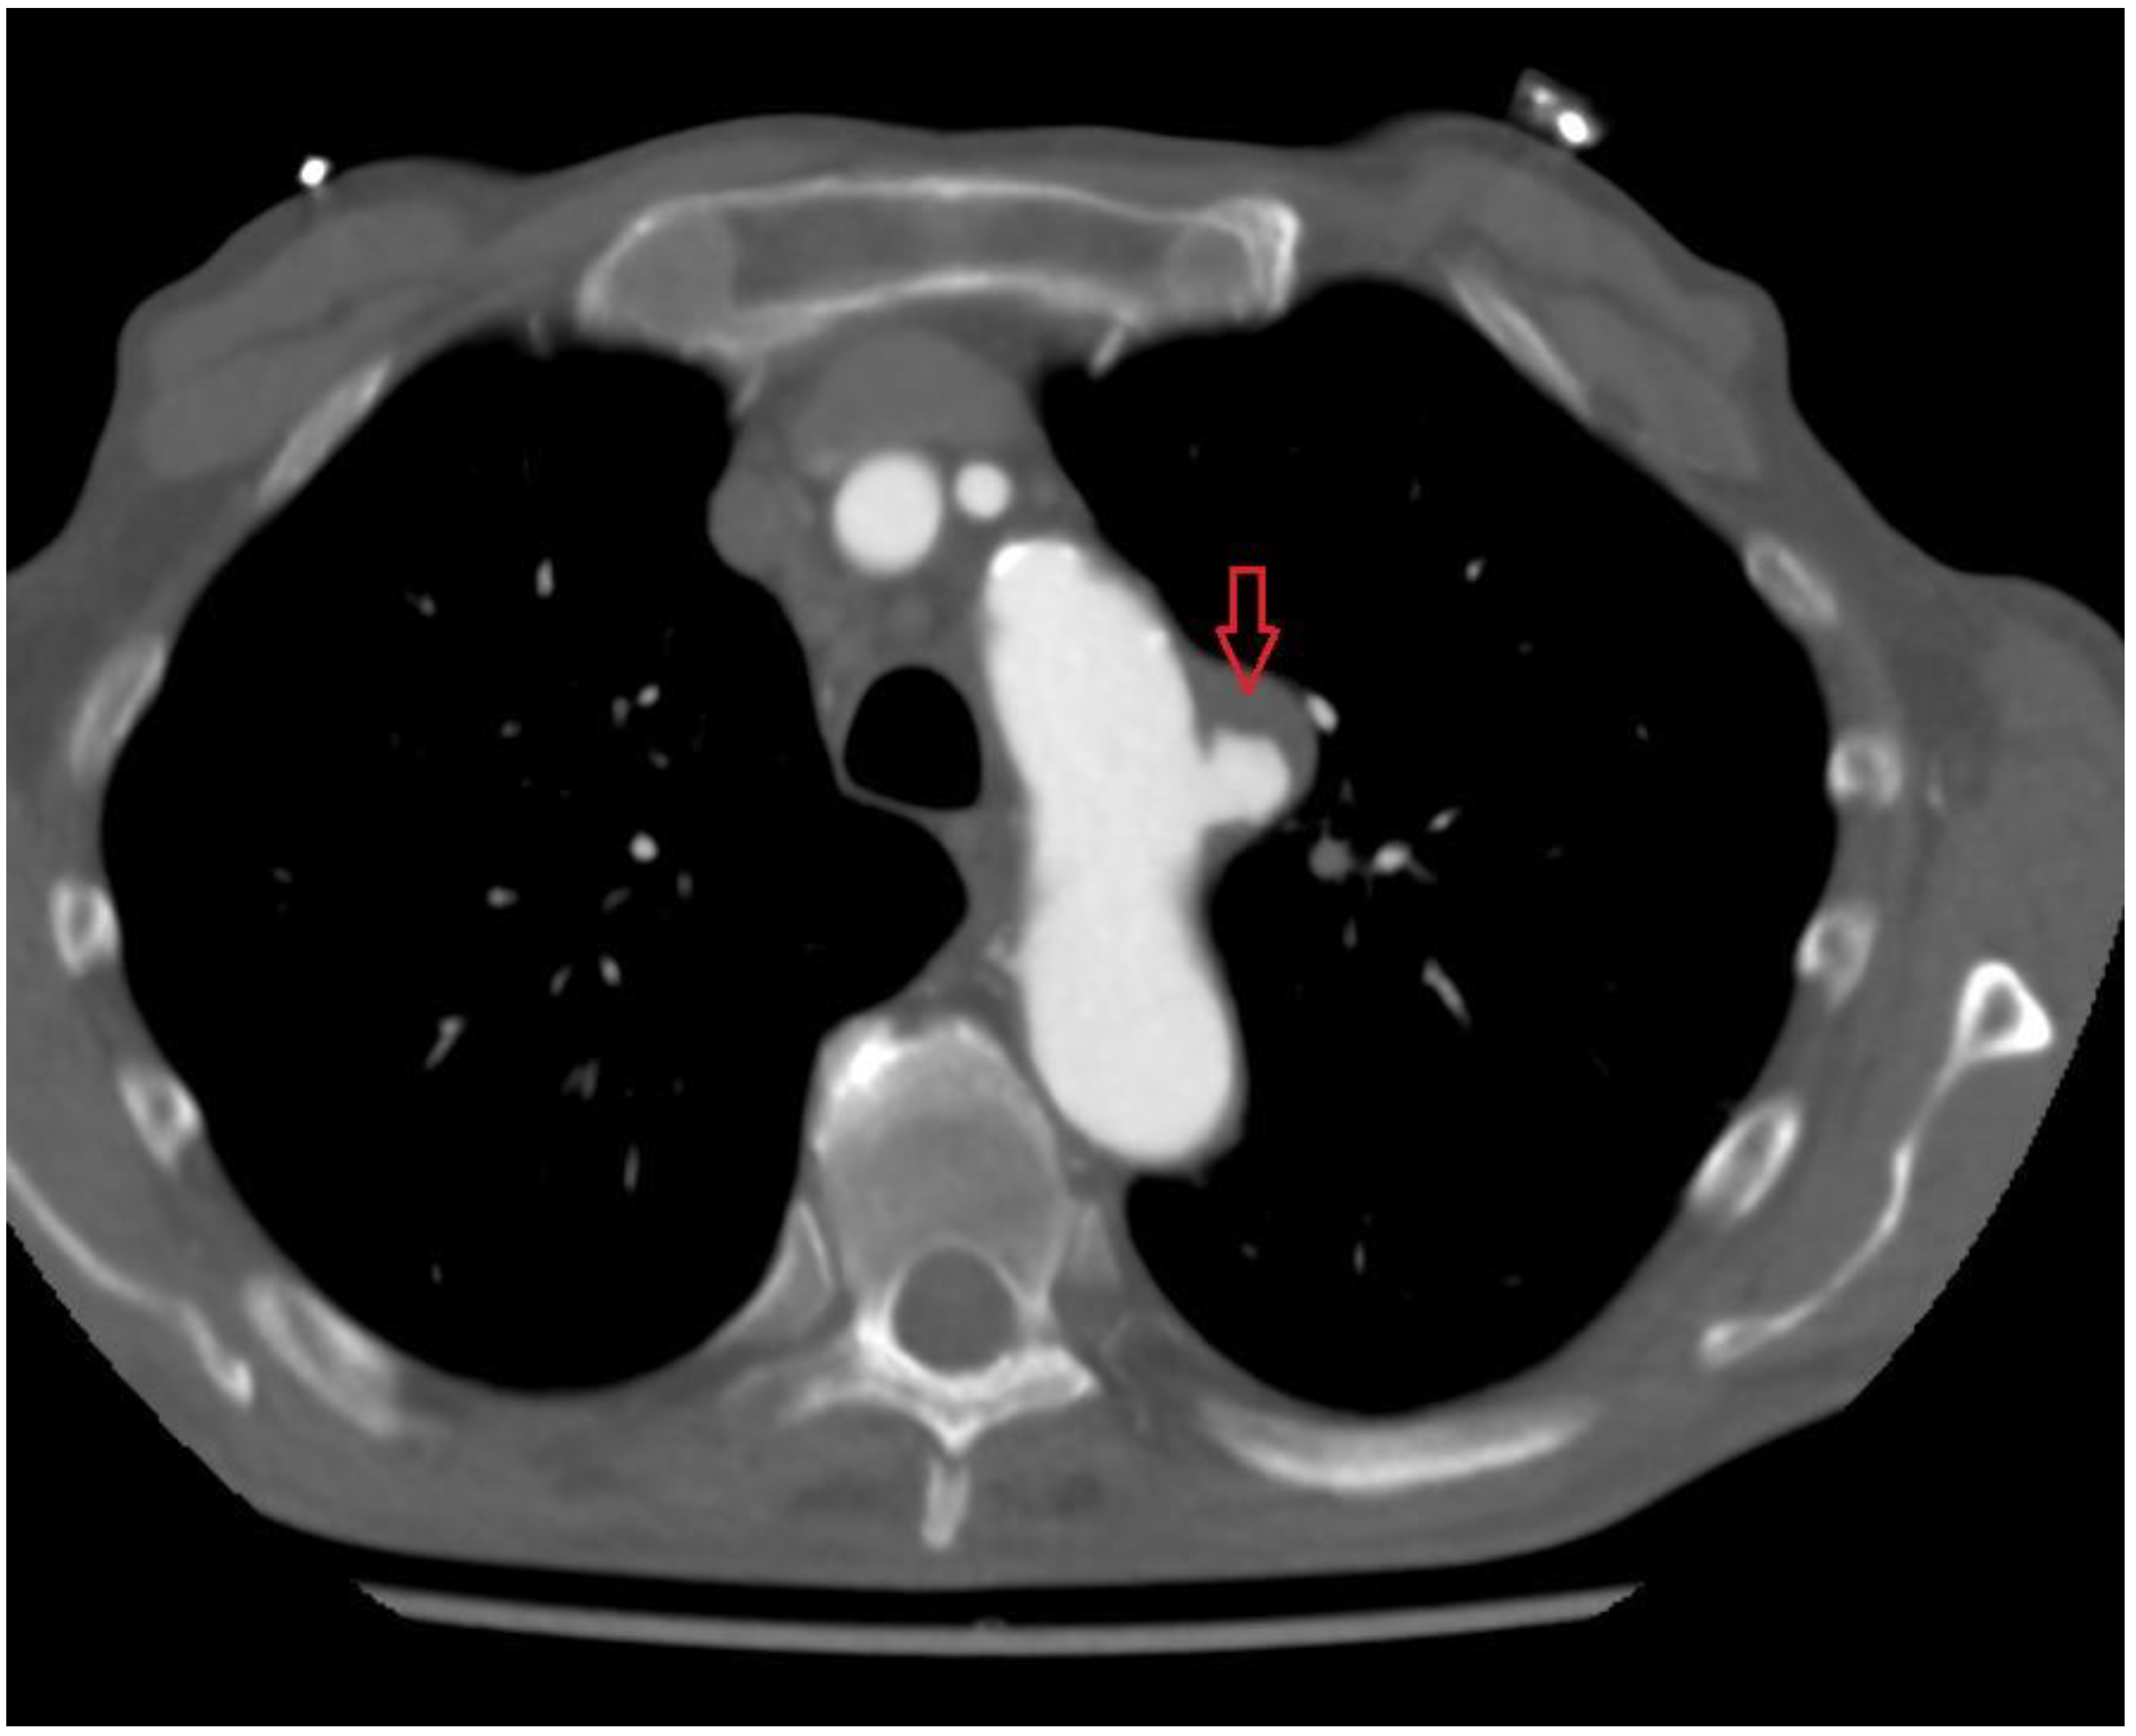

2. Case 1

A 79-year-old man with arterial hypertension, carotid artery stenosis and previous subdural hematoma presented in our hospital with an episode of transient chest pain radiating to his back; computer tomography showed this to be a penetrating aortic ulceration. After 2 years of follow up, the last computed tomography (CT) revealed intimal ulceration in the aortic arch. The lesion, a penetrating atherosclerotic ulcer, affected the left aspect of the patient’s aortic arch with diameter of 46 mm × 22 mm and height of 21 mm (Figure 1 and Figure 2), then the risk of progression to frank aortic dissection was large. Both the innominate artery and the left carotid artery were patent and free of dissection. The patient’s surgical risk was calculated as moderate–high, and thus we decided to perform an endovascular approach.

Figure 1. Preprocedural CT scan; red arrow shows PAU.